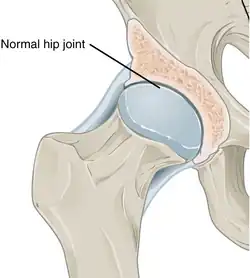

Annotated illustration of healthy hip joint

Healthy hip joint

Annotated illustration of hip joint with osteoarthritis

Hip joint with osteoarthritis[36]